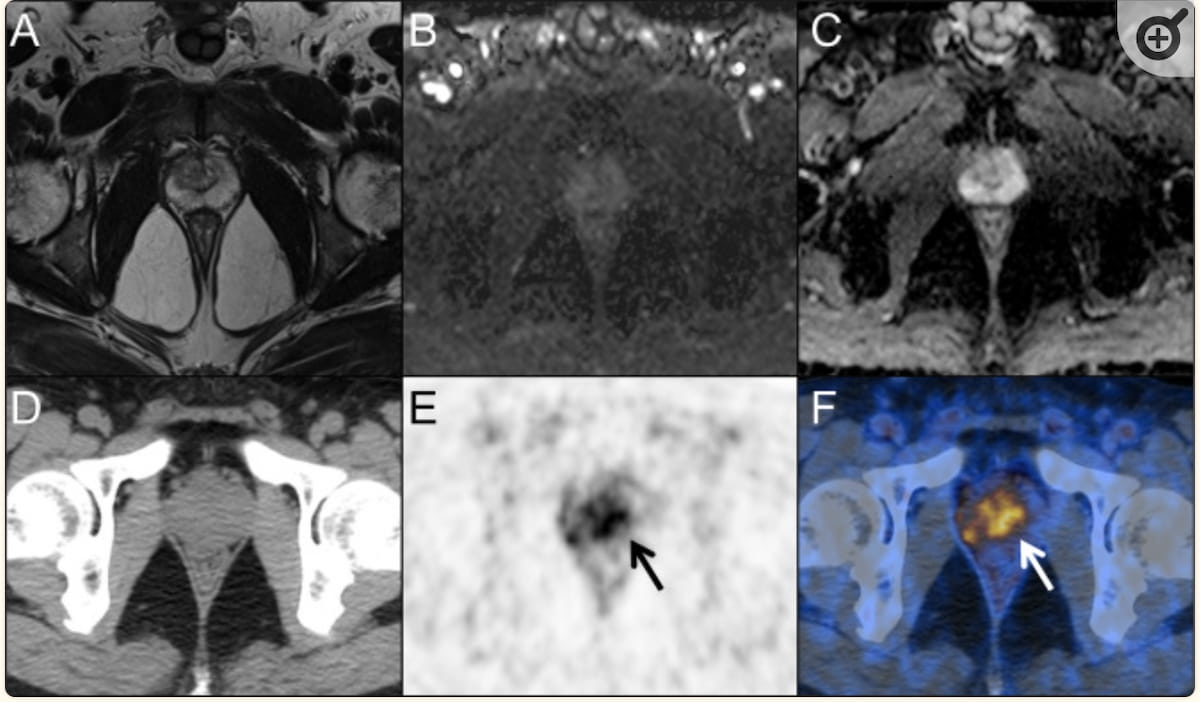

मैग्नेटिक रेजोनेंस इमेजिंग (एमआरआई) में 55 वर्षीय व्यक्ति में कोई घातक घाव नहीं दिखा (छवियां एसी) जिसमें एक वर्ष के दौरान पीएसए का स्तर 4.37 से 6.82 एनजी/एमएल तक बढ़ा हुआ था। हालाँकि, पॉज़िट्रॉन एमिशन टोमोग्राफी/कंप्यूटेड टोमोग्राफी (पीईटी/सीटी) छवियां बढ़ी हुई प्रोस्टेट विशिष्ट झिल्ली एंटीजन (पीएसएमए) को दर्शाती हैं (छवियों ई और एफ में तीर देखें)। बाद की बायोप्सी परिणामों से ग्लीसन स्कोर 4 + 3 प्रोस्टेट कैंसर का पता चला। (छवियां सौजन्य) कैंसर इमेजिंग.)